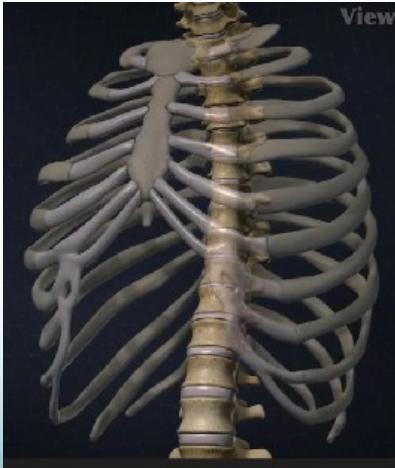

Basic Anatomy

Spinal Column Structure

Cervical Vertebrae

- Number: 7

- Range: C1 - C7

Thoracic Vertebrae

- Number: 12

- Range: T1 - T12

Lumbar Vertebrae

- Number: 5

- Range: L1 - L5

Regional Spine Characteristics

Thoracic Spine

- Lower thoracic not protected by ribs / more mobile

Lumbar Spine

- Main weight-bearing – very mobile